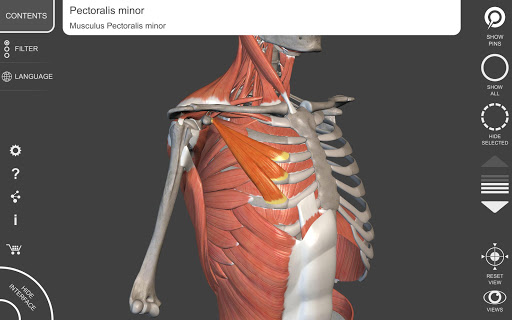

"Anatomy 3D Atlas" cho phép bạn nghiên cứu giải phẫu người theo cách dễ dàng và tương tác.

Thông qua giao diện đơn giản và trực quan, bạn có thể quan sát mọi cấu trúc giải phẫu từ mọi góc độ.

Các mô hình giải phẫu 3D đặc biệt chi tiết và có kết cấu lên đến độ phân giải 4k.

• Hệ thống cơ xương

• Xoay và phóng to từng mô hình trong không gian 3D

• Hình dung các cơ qua các lớp từ lớp nông đến lớp sâu nhất

• Bằng cách chọn một mô hình hoặc một ghim, thuật ngữ giải phẫu liên quan sẽ hiển thị

• Mô tả các cơ: nguồn gốc, chèn, chi phối thần kinh và hành động